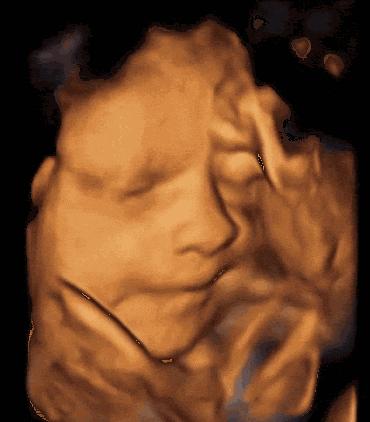

2、啃手指

在孕11周胎儿能做吸吮动作后,就会做出吸手指或嘬脚趾的动作。在宝宝出生后,如果妈妈细心观察就会发现,宝宝没事会经常吸手指,还是面带微笑,这其实就是宝宝把娘胎里的习惯带了出来,并持续下来。